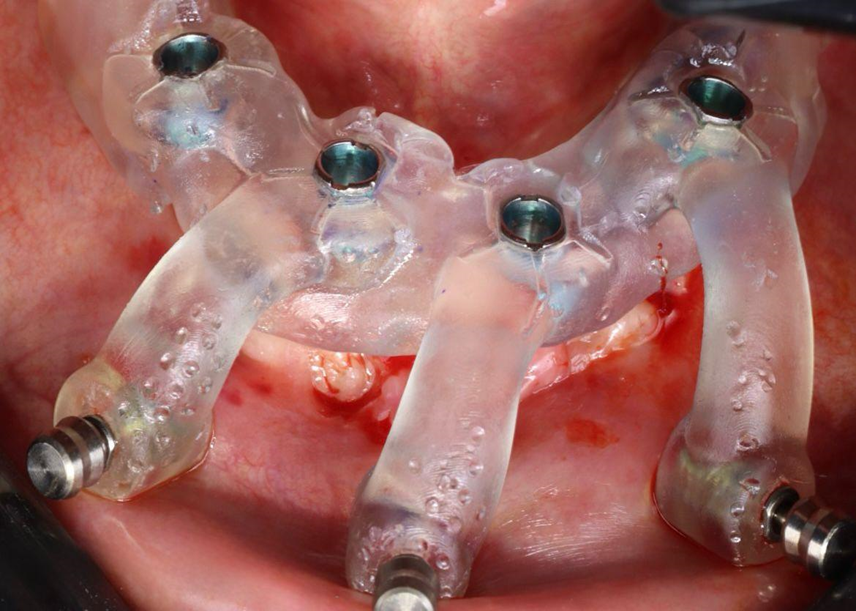

Paciente de 62 anos, do sexo feminino, sem comorbidades e história médica pregressa, apresentava severa reabsorção óssea em regiões anteriores e posteriores da mandíbula devido a uma peri-implantite (Figuras 1A e 1B). Feita a remoção dos implantes, a paciente optou por utilizar uma prótese total mucossuportada até a nova intervenção com prótese do tipo protocolo inferior. Após seis meses, a mandíbula encontrava-se cicatrizada (Figura 2). Como parte do protocolo diagnóstico, foi realizada tomografia computadorizada pela técnica do duplo DICOM. Com a severa perda óssea em região anterior de mandíbula, optamos por realizar a cirurgia de forma guiada, aumentando a previsibilidade e precisão da cirurgia. Os arquivos obtidos foram exportados para o software CoDiagnostiX, possibilitando a realização do planejamento reverso e o subsequente posicionamento virtual dos implantes (Figura 3). Com base no planejamento, optou-se pela instalação de quatro implantes Implacil Osstem CM AR Due Cone (3,5 x 7 mm), associados a mini-cônicos de 1,5 mm (Figuras 4A, 4B, 4C, 4D e 4E). A partir da tomografia da prótese da própria paciente, confeccionaram-se duas guias cirúrgicas: uma guia de pino de fixação (Figura 5) e uma guia de fresagem para a instalação dos implantes (Figura 6). Durante o procedimento cirúrgico, inicialmente foi posicionada a guia de pino de fixação para fresagem dos pinos de fixação e orientação da sequência cirúrgica (Figura 7). Após essa etapa, a guia foi substituída pela guia de fresagem dos implantes (Figura 8), utilizada para a fresagem e inserção dos implantes planejados (Figura 9). Concluída a instalação, optou-se por seguir o fluxo analógico, com a adaptação dos mini-cônicos 1.5 mm (Figura 10), realização da transferência de moldagem com silicona de adição leve e sutura com fio absorvível Vycril 6-0. O guia inicial foi adaptado com broca Maxicut, possibilitando sua utilização como molde de orientação para o laboratório protético (Figura 11). Após a moldagem, foram posicionadas as tampas de proteção sobre os implantes. Na fase protética, transcorridas 48 horas do procedimento cirúrgico, foi realizada a prova clínica da barra metálica e dos dentes (Figura 12). Na etapa subsequente, 72 horas após a cirurgia, procedeu-se à instalação e entrega do protocolo mandibular inferior e radiografia prévia, reabilitando funcional e esteticamente a paciente em curto espaço de tempo (Figuras 13A e 13B).